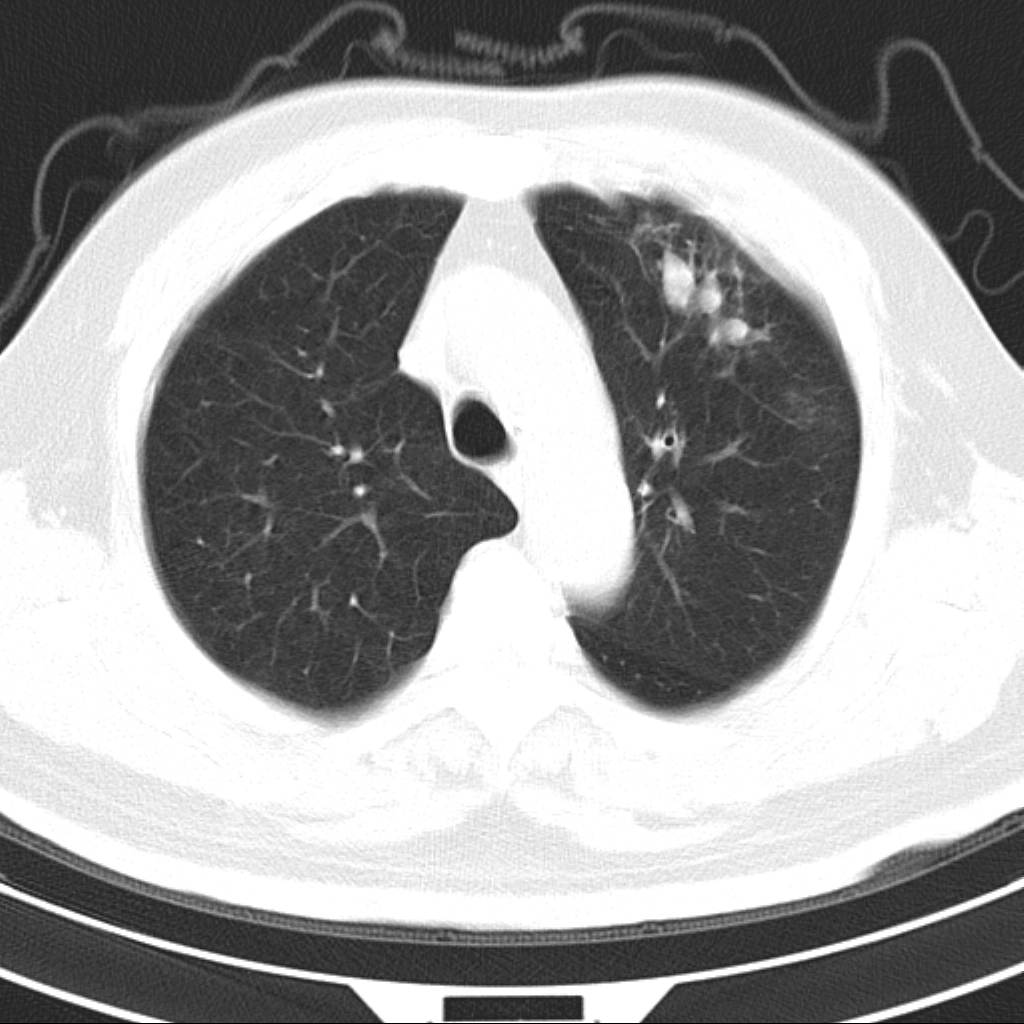

标题: CT18644:男,82岁,体检发现左肺阴影. [打印本页]

标题: CT18644:男,82岁,体检发现左肺阴影.

岁数太大,没有增强。麻烦见过的,给个诊断,顺便再说说病因

左侧中心型肺癌并粘液栓形成。很典型的。手套征。

支持 左肺上叶中央型肺癌并支气管内粘液栓形成。

尚不除外非感染炎症,过敏及哮喘曲霉菌病所致黏液栓塞,纸套征比较形象妾有一定特异性

考虑左肺上叶中央型肺癌并支气管内粘液栓形成。

支持 左肺上叶中央型肺癌并支气管内粘液栓形成,阻塞性肺炎

考虎左肺上叶中央型肺癌并支气管内黏液栓形成,不能增强是个遗憾,期待复查结果。

左肺上叶中央型肺癌